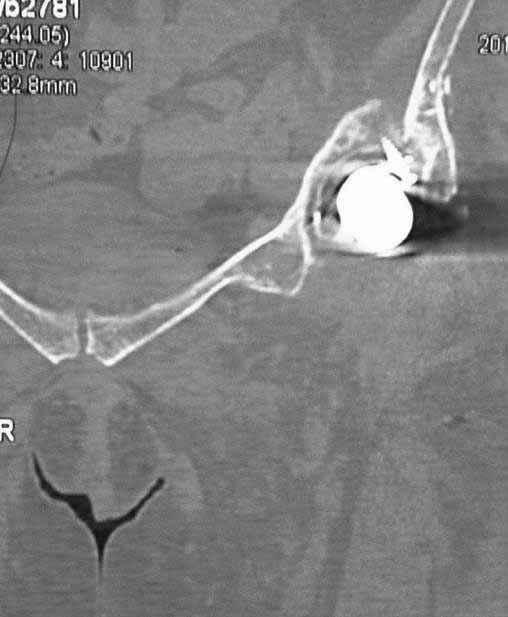

Пациентка 45 лет. Бесцементное эндопротезирование левого тазобедренного сустава 6 лет назад (впадина RM, Mathys, металл-металл, ножка Зульцеровская). За 10 лет до протезирования – коррегирующая остеотомия бедренной кости, которая не срослась в течение года до удаления пластины, а затем срослась в течение 3 месяцев иммобилизации в кокситной повязке. После протезирования получилось наблюдать пациентку почти постоянно, поскольку через 2 года синтезировал ей лодыжки на оперированной стороне, затем, через несколько месяцев удалил фиксаторы, а в 2009г. резецировал мениск на противоположной стороне. Боли все эти годы не беспокоили. Пациентка чуть выше среднего роста, вес тела нормальный. Физические нагрузки переносила хорошо. Работает на 7 этаже без лифта. Год назад экстирпация матки по поводу лейомиомы больших размеров. Несколько месяцев назад появились боли в области левого тазобедренного сустава. При рентгеновском и КТ исследованиях (июль с.г.) – нестабильность тазового компонента. От предложенной замены протеза пациентка на тот момент, слава богу, отказалась. Через какое то время боли в области левого тазобедренного сустава практически полностью прошли, а около 2 месяцев назад появилось ощущение патологической подвижности таза и боли в паху справа, которые через некоторое время уменьшились, а потом снова усилились после значительных физических нагрузок (много ходила по песку на пляже, носила тяжести). Ежедневно принимала диклофенак. На рентгенограммах – переломы правой лонной кости. Сейчас госпитализирована из-за болей в паху справа. Боли слева не беспокоят. На фоне снижения нагрузок в стационаре боли значимо уменьшились. Способна ходить без средств дополнительной опоры.

-правильно ли я расцениваю переломы как стрессовые на фоне неполноценного таза (pelvic insufficiency stress fractures)?

На представленных снимках тазобедренный сустав до и сразу после операции, затем 2 снимка 2009г., когда ничего не беспокоило, затем КТ 2-х месячной давности и вчерашние рентгенограммы обоих тазобедренных суставов.